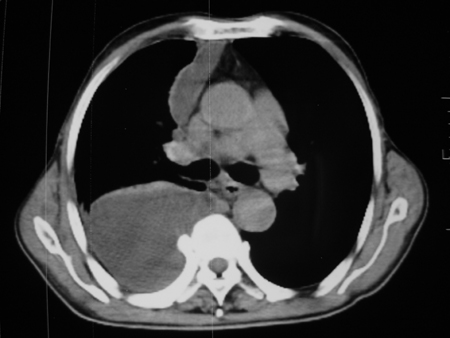

男77岁,胸痛就诊

右侧胸腔积液,部分包裹,右下肺膨胀不全,右下肺感染。

考虑右肺门占位并下叶不张 右胸包裹积液

右肺中叶及下叶炎症并胸腔积液(部分包裹),建议抽液后复查ct除外占位。